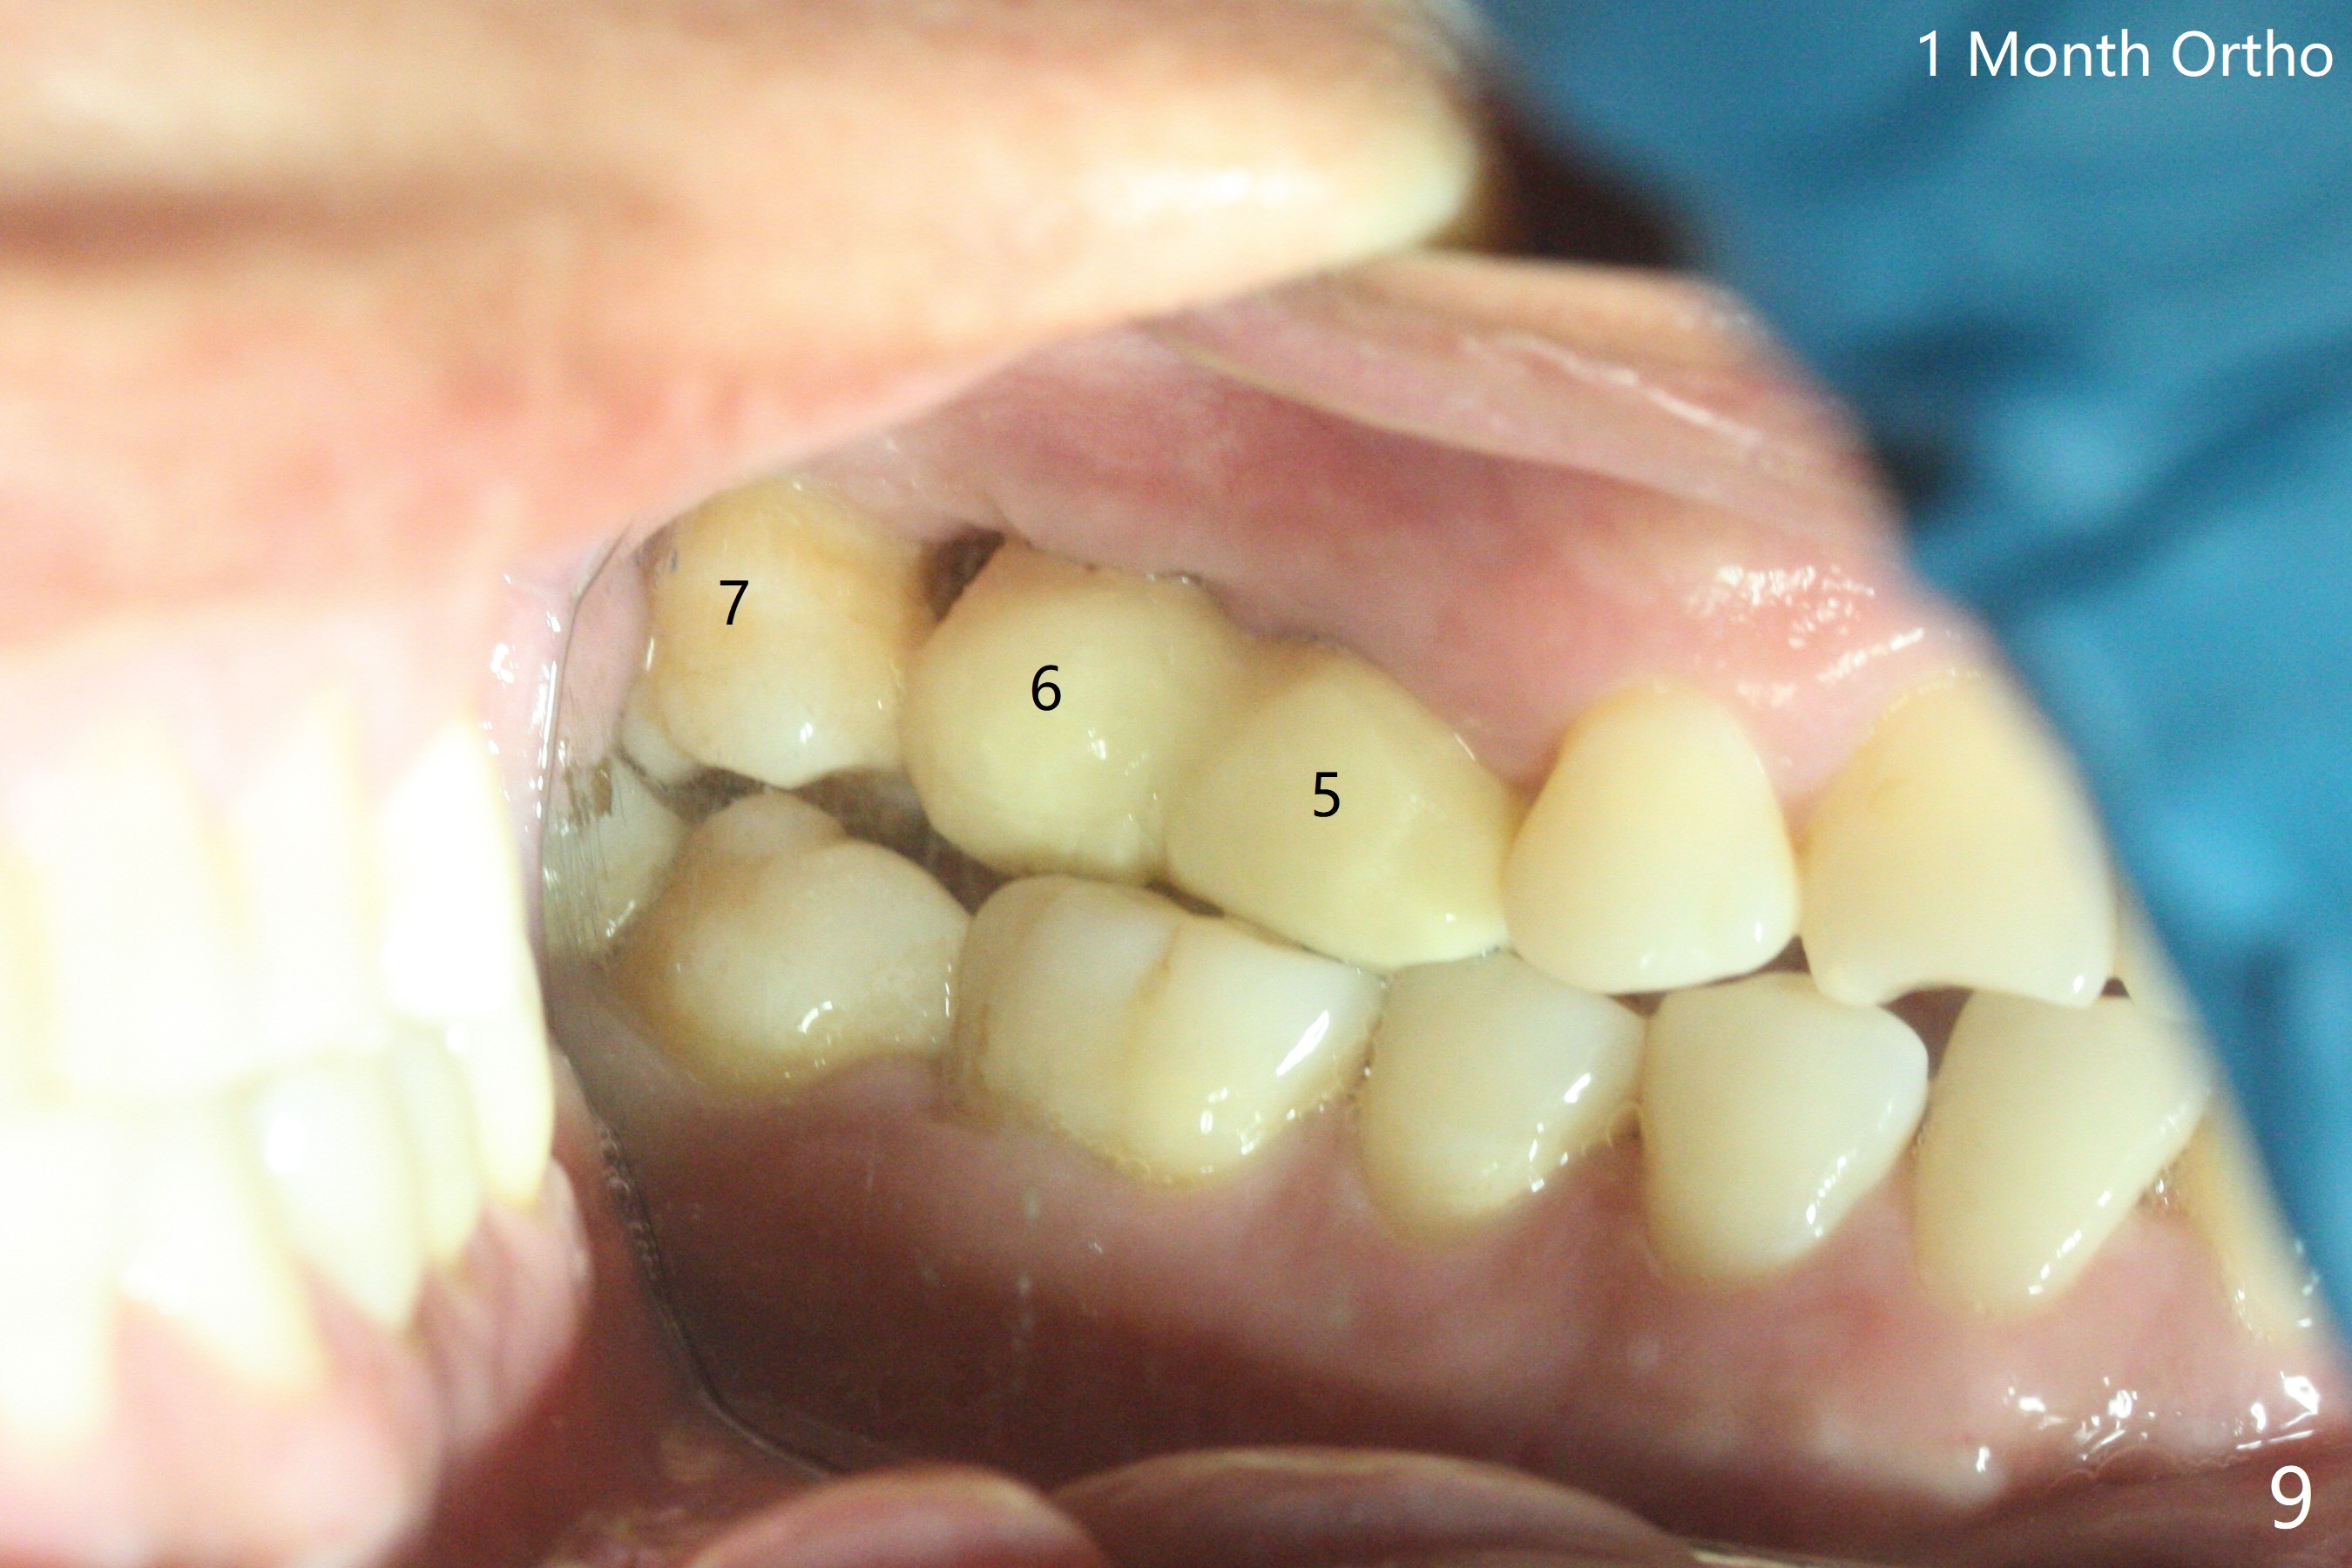

左上六植牙第三次失败后五个月,牙槽嵴宽度尚可,切开后放置导板,3.2乘19毫米园钻头好像接近上颌窦底板(图一),但是粘性骨块和4乘10毫米报废植体就不能进入上颌窦(图二),最后不得不使用3毫米Bicon骨凿,之后同一个报废植体就似乎进入上颌窦(图三),4.5乘8.5毫米正式植体植入深度和稳定性均正常(图四),腭侧植体稍微暴露,放置愈合螺丝后,放置骨粉和PRF膜,缝合,左上5植体放置5.7x4.5(4)毫米基台,固定牙周敷料。术后5.5个月植体好像整合(图五),缺牙间隙特别小,5临时牙冠(P)必须取出才能切开暴露植体,放置5.5x5毫米愈合基台(图六)。伤口愈合后,必须做渐进性负荷,之后做简单局部矫正,推7往远中,6缺失3年,7往近中倾斜移位。两周后牙周敷料脱落,伤口愈合,放置修复基台,故意将基台平面朝远中,足够空间制作临时牙冠(图七)。调整基台长度(比较图七,八)。制作连体牙冠(5,6),有意提高5牙冠高度,使左上7不与对合牙接触,有利于远中移位(图九)。也要在对侧提高咬合(图十)。局部矫正一个月后,磨去右侧咬合垫和磨短左上5,6临时牙冠,前牙还不能完全接触(图十一)。1-2星期前牙开合自行消失,取模做左上5,6牙冠。局部矫正似乎使左上7远中移位大约3毫米(比较图十二,十三)。粘固拧紧后(20 Ncm)14号牙牙冠咬合增高,拍摄根尖片(图十三),两个基台好像仍然完全就位,然后调整咬合。